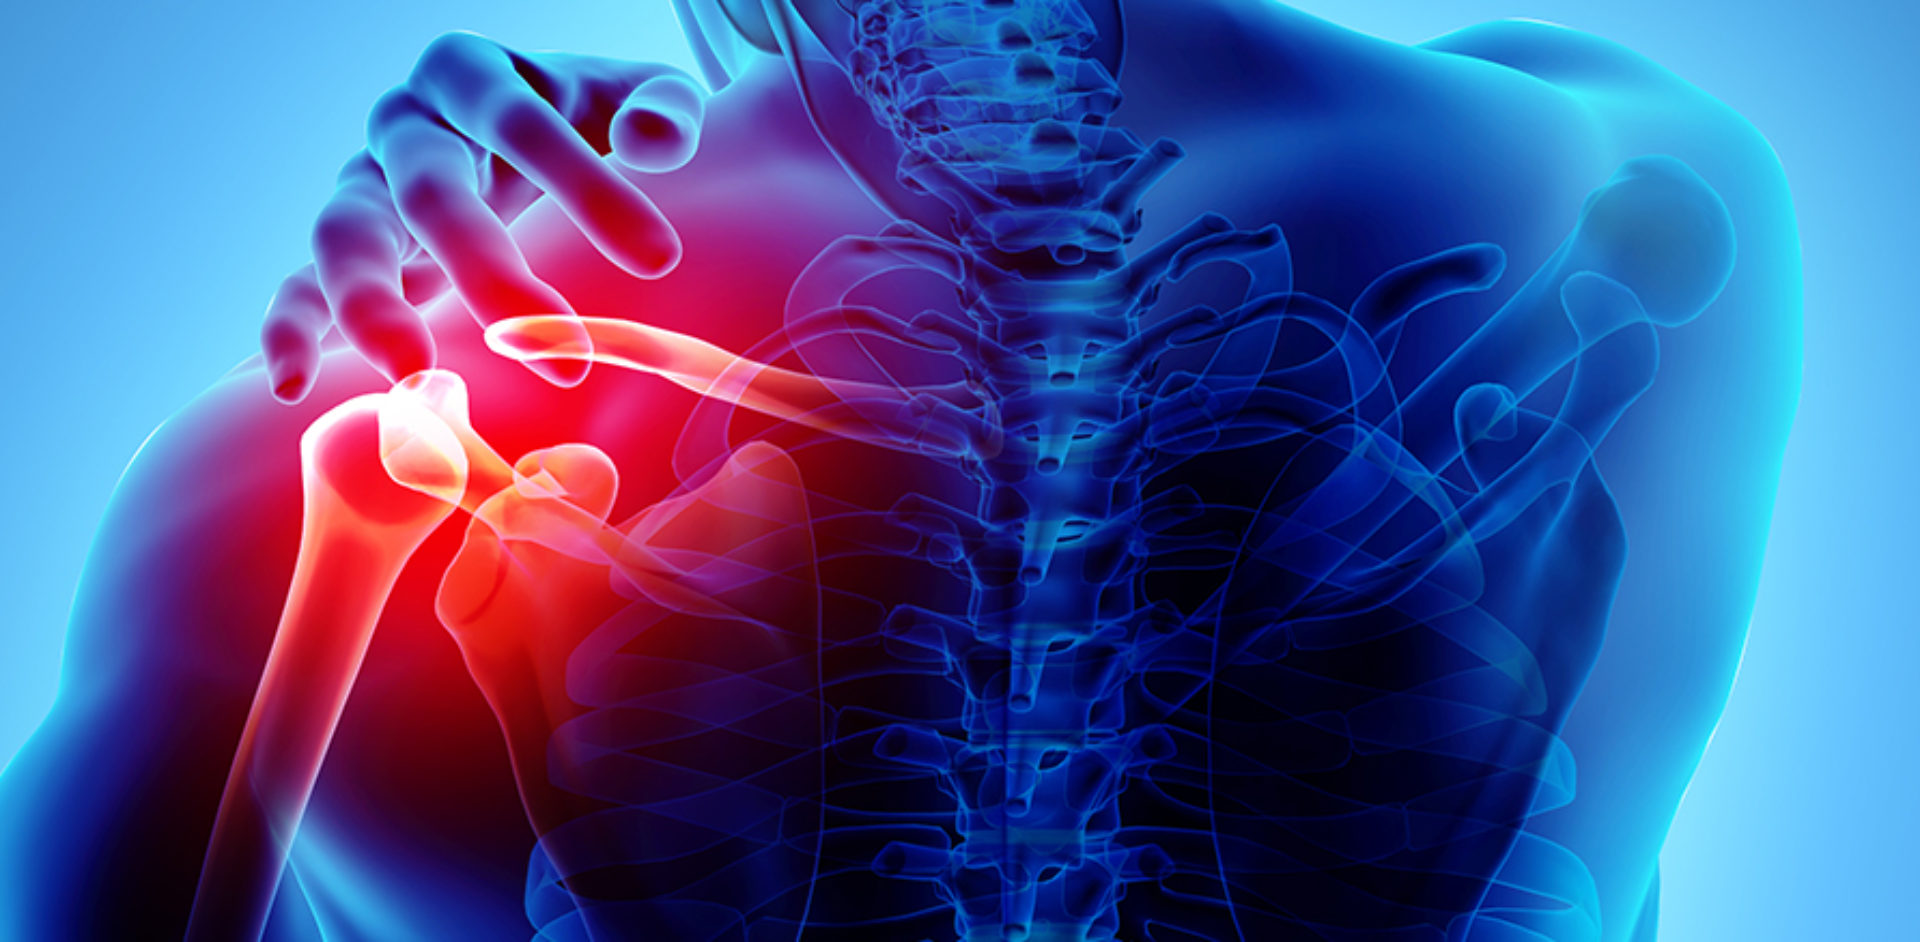

Traumatisme Sportive și Articulare

Traumatismele ortopedice includ o gamă largă de leziuni acute sau cronice:

- Luxații: umăr, rotulă, cot, gleznă – reducere și stabilizare

- Instabilitate capsulară: umăr recidivant, genunchi multidirecțional

- Rupturi tendinoase: tendon Ahile, rotulian, manșeta rotatorilor